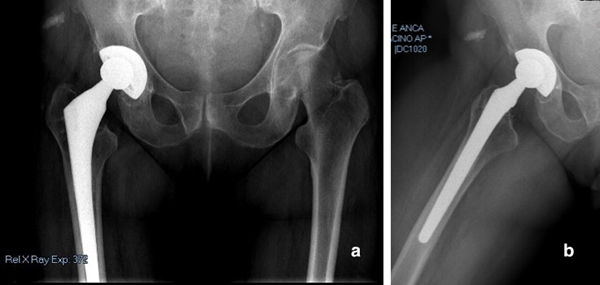

4:(a)整個骨盆的3D打印真人大小的塑料模型。 (b,c)特別是內(nèi)壁和后柱骨折。

在分析了3D圖像和3D打印的模型之后,他們將后壁骨折重新分類為不完整的后柱和內(nèi)壁髖臼骨折。此外,發(fā)現(xiàn)骨折是“自發(fā)性的”,骨儲備損失少于50%。最后,骨骼質(zhì)量圖確定了整體骨丟失,顯示后壁和內(nèi)壁的質(zhì)量均較差。 3D打印模型還用于執(zhí)行操作前模板?!爸委煵呗允歉鶕?jù)Simon等人提出的算法選擇的。 [14,1516],這表明髖臼翻修手術(shù)可以橋接或分散骨折,而無需固定骨折?!毖芯咳藛T解釋說。

63D建模數(shù)字重建。髖臼的后柱和內(nèi)側(cè)壁已修復(fù)。